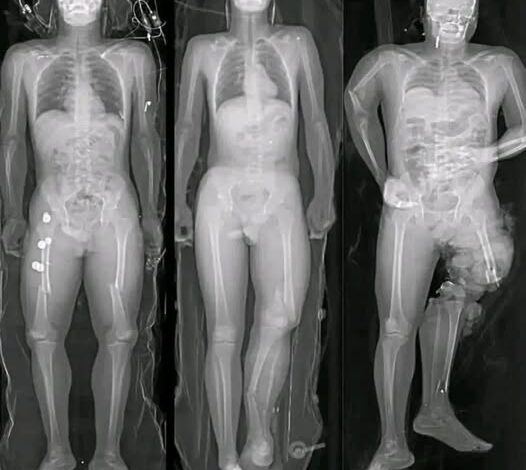

But what about the heart? The viral messages often latch onto a grain of truth and distort it beyond recognition. It is true that rare cases of myocarditis—inflammation of the heart muscle—and pericarditis—inflammation of the outer lining of the heart—have been reported, particularly in young men following the administration of mRNA vaccines. However, a “forensic” look at the data provides the necessary context that the viral posts omit. These cases are extremely rare, occurring in only a tiny fraction of the vaccinated population. Furthermore, the vast majority of these instances were categorized as mild. Patients typically responded well to standard medical treatment and rest, making full recoveries with no long-term impairment.

The real danger, which the sensationalist images never mention, is the virus itself. The risk of developing severe heart complications, including myocarditis, is significantly higher following a COVID-19 infection than it is following a vaccination. The virus does not just affect the lungs; it is a multi-systemic invader that can cause profound inflammation throughout the body, including the cardiovascular system. In this context, the vaccine acts as a shield, preventing the very heart damage that the viral posts claim it causes. To choose the vaccine is to choose a controlled, microscopic training session for your heart, rather than a full-scale, unmitigated war against a unpredictable pathogen.